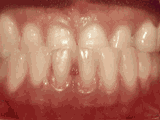

爱美之心,人皆有之~~5月份世界正畸日即将来临,暑假还远吗?分院提前给爱美的你准备好一份大大的福利,还等什么呢?抓紧约起来吧! 发现自己牙齿不整齐影响交际, 怎么还能与小伙伴愉快地玩耍? 无论是即将迈入新的年级还是即将面临找工作, 发现自己是“地包天”“龅牙妹”, 分分钟拉远自己和同龄人的距离! 这些难以启齿的牙齿问题, 想想就让人心碎,怎么办呢? 不要着急,不要慌乱! 这个时候, 你可能需要的就是牙齿矫正了~! 以下图片告诉你, 这些情况都适合去做牙齿矫正哦~! 前牙移位 症状表现:牙齿缺失、牙周疾病等导致相邻牙齿无秩序前突 牙列拥挤 症状表现:牙齿过多,牙槽骨过窄,使牙齿没有足够空间生长造成牙齿排列不齐 开颌 症状表现:通俗来讲就是咬牙时无法紧闭,上下牙齿中间有缝 上牙深覆合 症状表现:上牙边沿覆盖下牙超过1/3,俗话说的天包地 后天牙列稀疏 症状表现:疾病外因等造成的牙列稀疏,牙槽骨过长或牙齿缺失,导致排列太宽松,零零散散 前牙反合 症状表现:下牙边沿覆盖上牙超过1/3,俗话说的地包天 天生牙列稀疏 症状表现:天生的牙列稀疏,牙槽骨过长,牙缝过宽、牙齿较少(一般不缺牙),导致排列宽松,零零散散 以上几种情况有你么? 要知道一口整齐的牙齿 绝对能够把整体的颜值提升N个档次! 如果你不幸中招, 就好好利用这个正畸月, 来分院加入到正畸大军里吧! 牙齿正畸也叫做牙齿矫正,原理简单来讲呢,就是对牙齿施加一个合适的外力(一般通过矫正器来施加),这个力会通过牙齿传递到牙齿周围的牙槽骨上,使得代谢很活跃的牙槽骨发生改建,从而带动牙齿一起缓慢移动。其治疗效果有着肉眼可见的强大变化! 借此正畸月,分院为大家准备了正畸月大放价,暑假提前约的活动!!!如果还想了解更多关于牙齿矫正的信息,欢迎大家来到分院进行咨询哦~我们的专业团队会帮您定制最适合自己的矫正方案,活动月矫正方案免费送哦!定能助您改“斜”归“正”!露出灿烂自信的笑容!